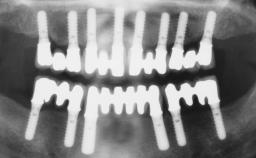

Immediate Loading of Six Implants in the Maxilla and Final Restoration with a Full-Arch Gold/Ceramic FDP Involving the Concept of Tilted Implants

A 61-year-old male patient with a failing fixed maxillary rehabilitation and a fixed mandibular rehabilitation requested a new fixed maxillary rehabilitation. The patient was wearing a temporary metal-reinforced maxillary bridge inserted two years before the consultation. He reported that his previous dentist did not want to insert a definitive framework because he considered the residual teeth to have a negative prognosis. The patient reported a history of recurrent caries and endodontic complications as the main reason for the previous extractions. The anamnesis was negative for periodontal disease and bruxism. The patient’s chief compliant was the mobility of his maxillary prosthesis, which needed to be re-cemented frequently, and discomfort during chewing.Moreover, the patient was not satisfied with the esthetic appearance of his maxillary teeth, which he found too long. The patient asked for a stable and comfortable fixed maxillary rehabilitation and firmly rejected any removable solution.

# of Implants 6

Type of Implants One-Piece|Reduced-Diameter

Bone Augmentation Horizontal|Simultaneous

Defining Characteristics Fully edentulous upper jaw to be rehabilitated with four or more implants

Modality Fixed hybrid bridge on 5+ implants

Bone Volume Deficient horizontally, allowing simultaneous augumentation